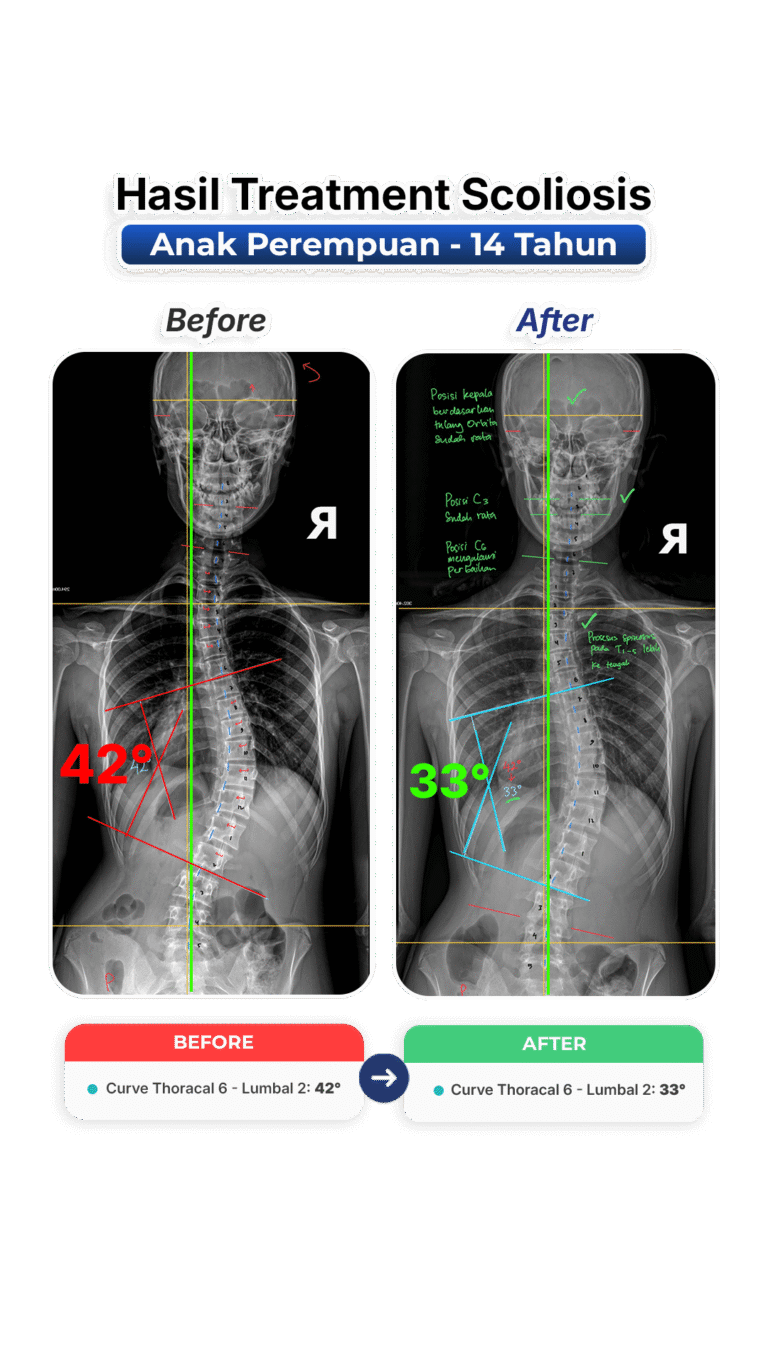

Perubahan nyata setelah mengikuti program terapi skoliosis di VLife Medical Galaxy Mall 3.

Perawatan scoliosis dilakukan melalui evaluasi tulang belakang menyeluruh, program terapi bertahap, fokus keseimbangan postur, mengurangi nyeri, memperlambat progres kelengkungan, serta meningkatkan fungsi gerak harian pasien secara aman dan terkontrol medis.

Penanganan skoliosis berbasis evaluasi postur menyeluruh, terapi manual khusus, latihan koreksi, serta pemantauan progres di setiap sesi. Dibuat untuk remaja dan dewasa yang ingin mengendalikan kelengkungan skoliosis dan mengurangi nyeri.